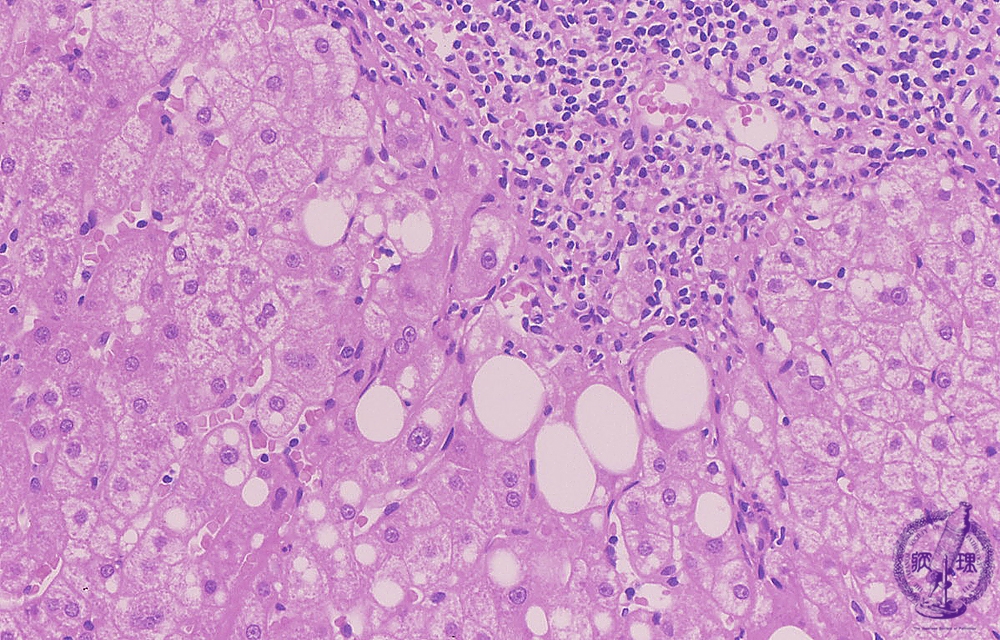

Microscopic image (HE stain, high power view): There is dense portal chronic inflammation with interface hepatitis comprising lymphocytic inflammation at the limiting plate and concurrent hepatocellular drop-out (yellow box). Hepatocytes contain large cytoplasmic lipid droplets (steatosis).